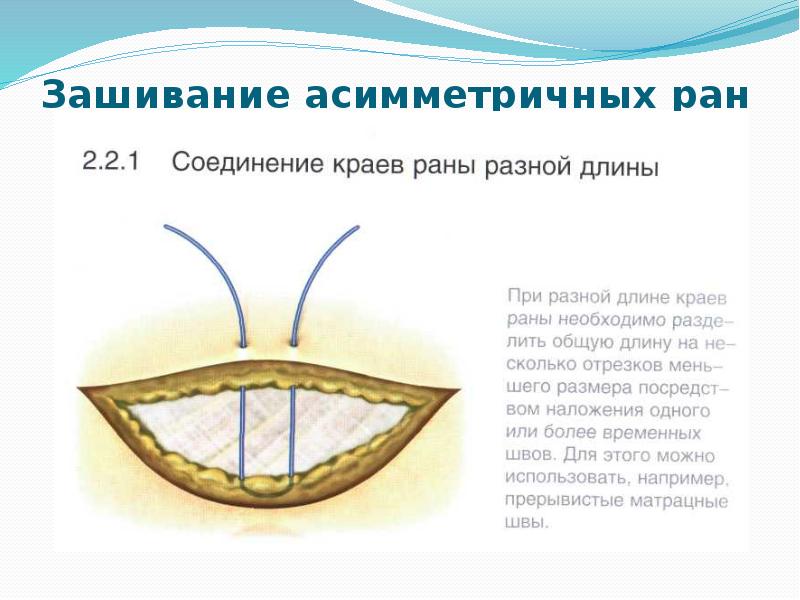

- 46. Зашивание асимметричных ран